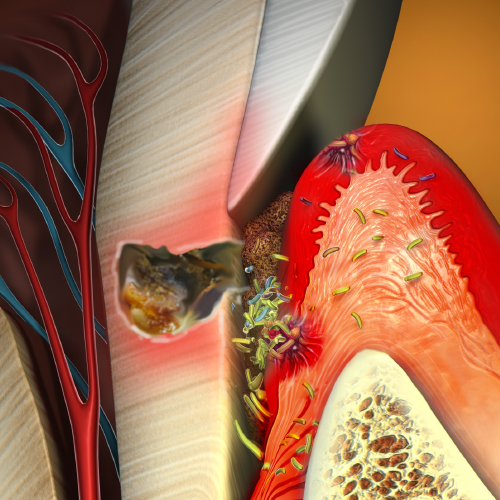

Infection Control: Current Topics

Monday, March 27, 2023

This eBook provides two continuing education (CE) articles on infection control. The first CE article describes dental water safety. Intended to help dental practices perform dental-unit water-line (DUWL) testing, this article discusses modes of microbial transmission in dental environments and desc...

Innovations in Infection Control in Dentistry

Thursday, December 22, 2022

This Compendium eBook offers a continuing education (CE) article on the use of personal protective equipment (PPE) for infection control in the dental setting. This eBook also includes a report of an in vitro study evaluating the effectiveness of a SARS-CoV-2 virucidal oral rinse. Download ...

Infection Control Standards in the Dental Setting

Katrina M. Sanders, RDH, BSDH, MEd, RF

Thursday, July 22, 2021

The current global coronavirus disease 2019 (COVID-19) pandemic has provided dental professionals with a critical opportunity for understanding the process by which infection occurs. Known as the “chain of infection,” this process is a specific cascade of events that must occur in sequence in or...

Microbes and Their Role in the Oral-Systemic Connection: A Review of Recent Literature

Sanda Moldovan, DDS, MS, CNS

Friday, December 11, 2020

This Compendium eBook features a continuing education (CE) article presents recently reported associations between oral and systemic health, as well as mechanisms recently uncovered through which oral bacteria influences systemic conditions.

Bioactive Restorative Materials in Dentistry

Monday, September 9, 2019

This Compendium eBook features a continuing education (CE) article that focuses on potential benefits of materials used for direct restorations with claims of bioactivity.

Spotlight on Infection Control in Dentistry

Thursday, August 15, 2019

This special Compendium eBook delivers a brand-new CE article on infection control, along with a peer perspective presenting additional information on disinfection measures.

Today's Trends in Infection Control

Friday, April 26, 2019

This special Compendium eBook provides two articles on infection control. The first is a continuing education (CE) article on preventing infection and injury by using personal protective equipment, with an emphasis on eyewear. The second article covers dental unit waterline contamination by...

Advances in Infection Control

Friday, November 16, 2018

This special Compendium eBook provides a continuing education (CE) article designed to help dental professionals understand the danger of waterborne pathogens and the importance of testing, disinfecting, and maintaining dental water lines to avoid contamination from microbe-containing biofi...

Updates in Infection Control

Monday, November 20, 2017

This special Compendium eBook provides a continuing education article that explains the value of dental office employees wearing personal protective equipment (PPE). Additionally, the eBook provides two other articles on infection control topics, one on the importance of having a designated infectio...

Infection Control

Monday, February 27, 2017

Clinicians must be diligent when treating patients, and similarly, need to be vigilant about the condition of their offices and operatories in regard to inhibiting infection control. This eBook is aimed at assisting clinicians in their endeavors to combat contamination. Download to earn 4 FREE CEU!